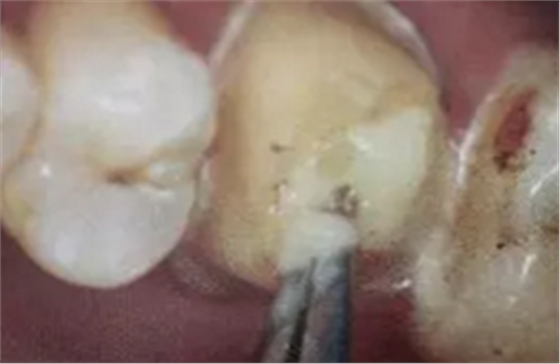

單純的使用三用槍即使反復(fù)沖洗液難將根管內(nèi)的酸蝕劑沖洗盡,尤其是后牙根管。

(冠部及根管全酸蝕)

(三用槍沖洗)

(注射器沖洗)

(根管毛刷清洗)

臨床建議用注射器、三用槍和柱狀毛刷,三者聯(lián)合反復(fù)沖洗。如再配合超聲波振蕩沖洗更佳。